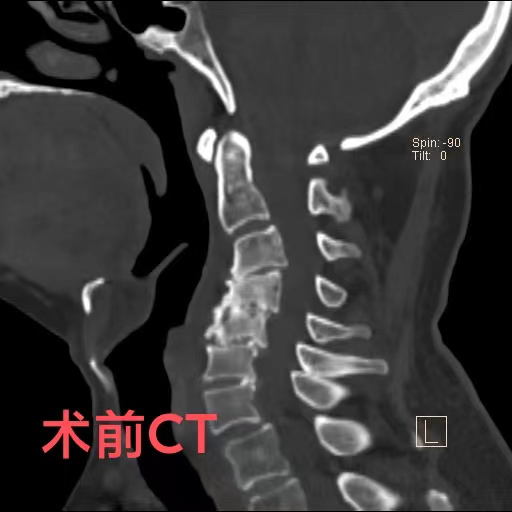

近日,74歲的陳爺爺,由于出現頸部疼痛、手腳麻木、行走困難等癥狀被家人送到重慶醫科大學附屬璧山醫院(重慶市璧山區人民醫院)康復醫學科就診。科室羅秋紅主治醫師為其進行了頸椎核磁共振檢查,結果提示,患者頸椎變形已導致脊髓神經受壓,隨時有高位截癱的風險。陳爺爺患有頸椎病多年,因擔心手術帶來的風險,長期依靠理療來緩解病痛,這次也是因為癥狀日趨嚴重,無奈之下才前來就醫。

羅醫生第一時間聯系了神經外科脊柱脊髓組的鄧雷主治醫師。針對陳爺爺及其家屬的擔憂,鄧雷主治醫師進行了耐心細致的溝通,最終陳爺爺決定配合醫護進行手術治療。患者高齡且有基礎疾病,手術方案需要慎之又慎。神經外科副主任(主持工作)徐忠燁主任醫師組織全科醫生根據患者具體病情,制定了最終方案:前路3節段頸椎間盤切除+頸椎后凸畸形矯正。

陳爺爺長期的頸椎變形產生了大量骨質增生,給術中的鄧雷、蔣登志醫生出了難題。在神經顯微鏡下,他們的眼睛如鷹,指尖之中飛舞最溫柔的神經刀鋒,雕塑著最堅硬的頸椎驁骨。最終,手術耗時兩個半小時,成功矯正,沒有神經損傷!患者術后3天康復出院。